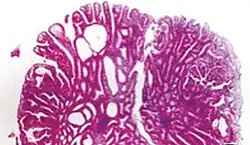

| Tubulovillous adenoma | 20% to 25%[15] | 25–75% villous[14] |

| |

- Tubulovillous adenoma: 20% risk of cancer